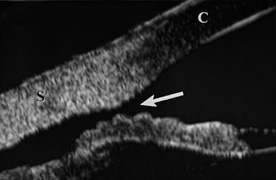

CORNEA Abrasions of the corneal epithelium are common but because they heal rapidly, they are of little consequence. Endothelial damage can be more serious. A local concussion (coup effect) can rupture endothelial cells and loosen the intercellular tight junctions. They can also be damaged by being crushed against the iris and the lens. The transient corneal edema usually clears, but endothelial damage can be permanent. Follow-up studies of patients with traumatic hyphema show endothelial cell loss that correlates with the severity of the initial injury.28,29 When a total hyphema is present, the damaged corneal endothelium may permit hemoglobin to enter the corneal stroma. Usually, high intraocular pressure is required to cause corneal bloodstaining, but cases have been reported in which the intraocular pressure was normal.30 Corneal transplantation is rarely necessary as the bloodstaining nearly always clears spontaneously, but this may require a considerable period of time. The central cornea clears last. Adults can wait for clearing, but in young children, amblyopia can develop. When the cornea is abruptly forced backward by severe blunt trauma, it presses the iris against the lens, preventing the escape of aqueous into the posterior chamber. If enough force is applied, the entrapped aqueous dissects into the ciliary body, resulting in a recessed angle (Fig. 4). This tearing of the ciliary body is responsible for approximately 90% of the hyphemas seen after blunt trauma.31,32 Other causes of hemorrhage include separation of the iris from the ciliary body (iridodialysis) and sphincter tears. Ultrasound biomicroscopy can be useful in diagnosing dissection of the ciliary body or iridodialysis (Fig. 5).33–35